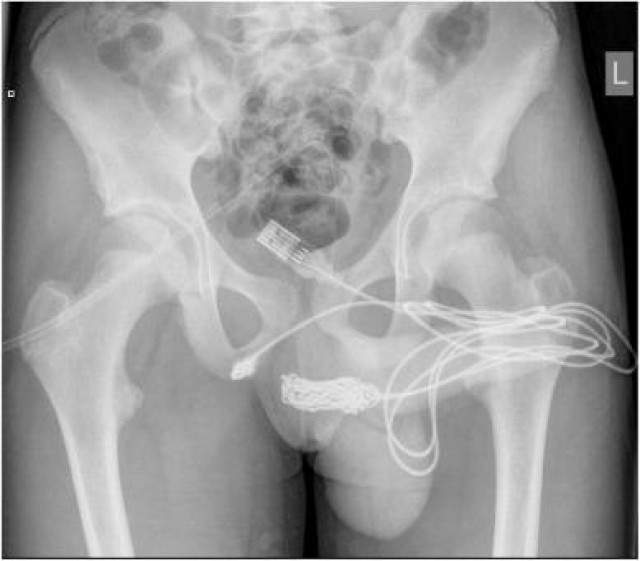

Un noi de 15 va acabar a urgències a Londres després d’intentar-se medir el penis amb un cable USB. El jove es va introduir el cable dins la uretra, tal com es pot veure a les radiografies, i va haver de ser intervingut.

Els metges van haver de tallar un múscul de la zona del penis per poder-li extreure.Per sort, la cirurgia va anar bé i el noi va rebre l’alta.